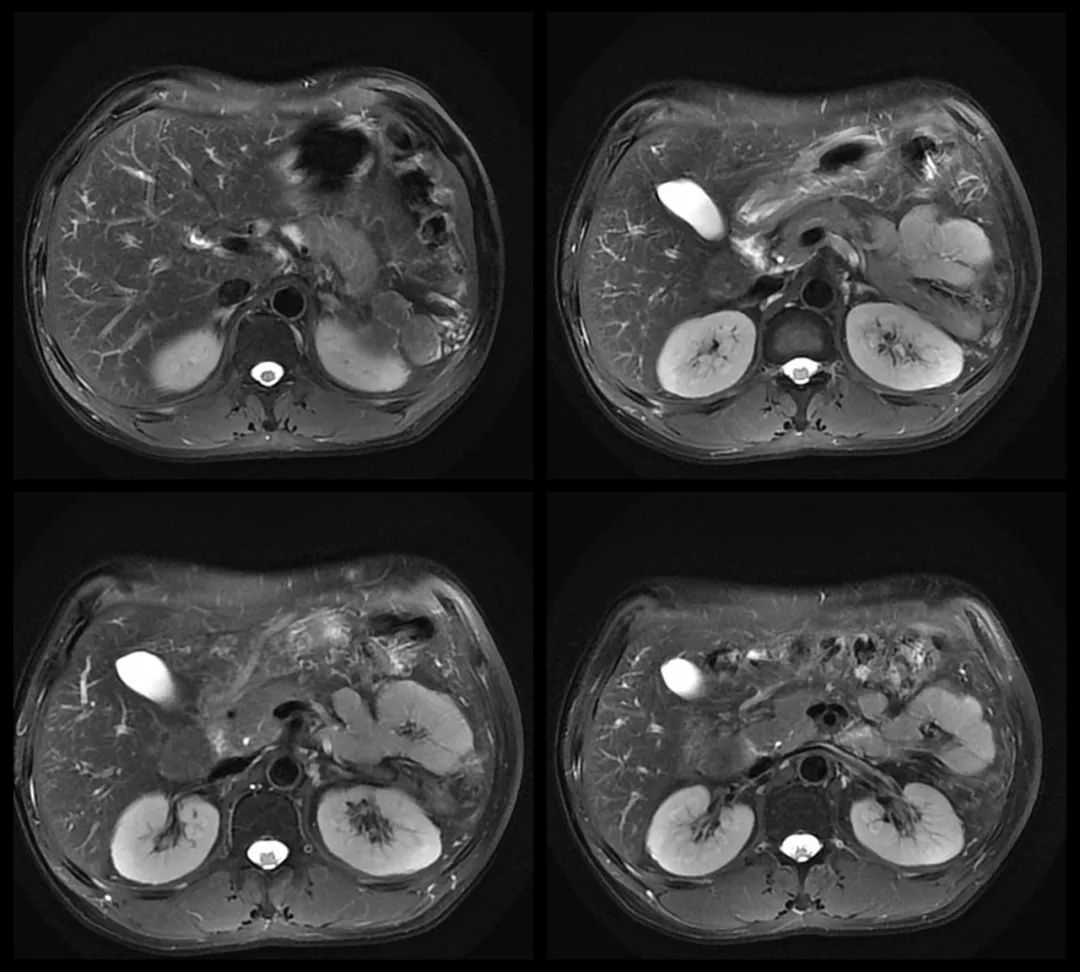

MRI:

MR:多数表现为 T1WI 稍低信号,T2WI 中高信号,与正常脾组织信号相似。增强扫描动脉期、门静脉期和延迟期均为高信号。